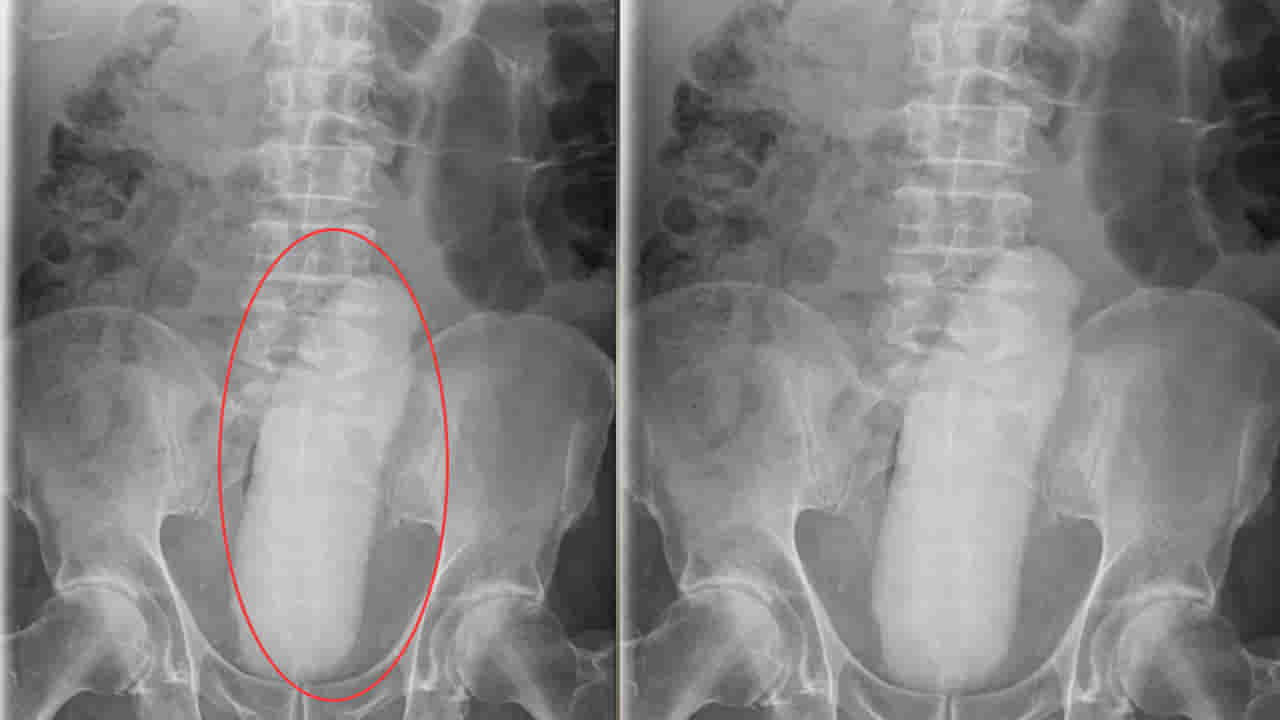

వివరాల్లోకి వెళ్తే.. మధ్యప్రదేశ్లోని ఓ వ్యక్తి శరీరంలో నుంచి 16 అంగుళాల పొడవైన విదేశీ వస్తువును డాక్టర్లు తొలగించారు. గతేడాది జూలై 21న ఛతర్పూర్ జిల్లా ఆస్పత్రిలో త్రీవమైన కడుపునొప్పితో ఓ రైతు అడ్మిట్ అయ్యాడు. ఆస్పత్రిలోని వైద్యులు అతడికి టెస్టులు చేయగా.. శరీరంలో విదేశీ వస్తువు ఉన్నట్టు కనుగొన్నారు. అది ఎలా శరీరంలోకి చేరిందో తెలియదు గానీ.. దాన్ని శస్త్రచికిత్స ద్వారా తొలగించారు. సుమారు రెండు గంటల పాటు ఆపరేషన్ చేసి.. ఆ విదేశీ వస్తువును తొలగించారు. ఆ విదేశీ వస్తువు వల్ల సదరు రోగికి ఇంటర్నల్గా డ్యామేజ్స్ చోటు చేసుకున్నాయని డాక్టర్లు తెలిపారు. రోగి మానసిక ఆరోగ్య సమస్యలతో బాధపడుతున్నాడని.. అందుకే ఇలా శరీరంలోకి సొరకాయని చొప్పించి ఉండొచ్చునని అన్నారు.